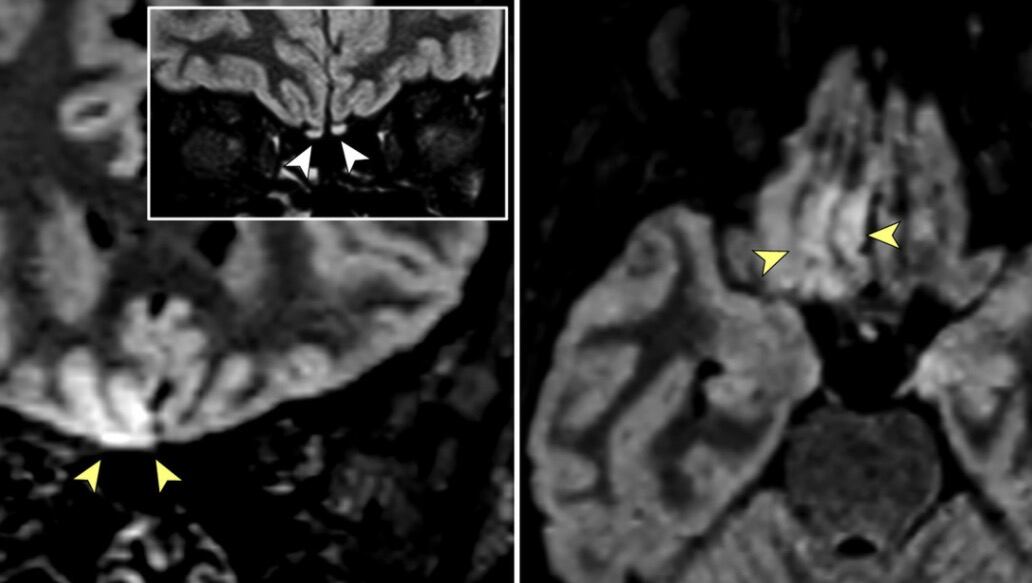

En imágenes tridimensionales y bidimensionales de recuperación de inversión atenuada por líquido, se evidenció una hiperintensidad cortical en el giro recto derecho y una hiperintensidad sutil en los bulbos olfatorios.

En consecuencia, durante una resonancia magnética de seguimiento realizada 28 días después, la alteración de la señal en la corteza desapareció por completo y los bulbos olfatorios eran más delgados y un poco menos hiperintensos. Por ende, la mujer se recuperó de la anosmia y no se observaron anomalías cerebrales.